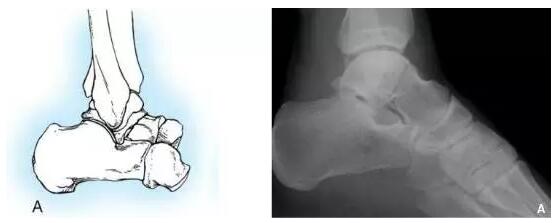

HawkinsⅠ型:距骨颈骨折无移位